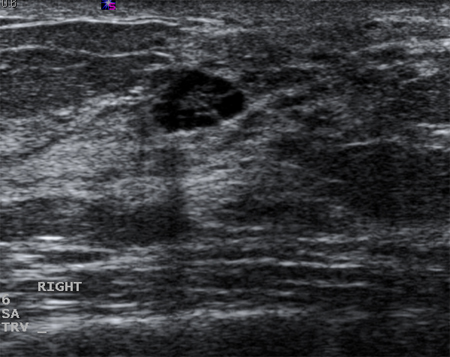

Los quistes que vuelven a aparecer o que no se resuelven por completo mediante aspiración deben someterse a biopsia para descartar una neoplasia maligna. De forma similar, debe plantearse la posibilidad de realizar una biopsia en casos de quistes complejos o que posean elementos sólidos. Las características sonográficas pueden clasificar una masa sólida como "probablemente benigna" o "sospechosa". Las masas que son lisas, ovaladas, lobuladas, con márgenes claramente definidos y cuyo ancho es superior a su altura suelen ser benignas (p. ej., fibroadenoma). Si una masa es irregular, heterogénea, posee márgenes mal definidos o espiculados y su altura supera a su ancho, se considera "sospechosa" de neoplasia maligna y debe realizarse una biopsia.[Figure caption and citation for the preceding image starts]: Imagen en ultrasonografía de un quiste complejoCortesía del Dr. Lane Roland, University of Louisville; utilizada con autorización [Citation ends].

[Figure caption and citation for the preceding image starts]: Imagen en ultrasonografía de un carcinoma invasivoCortesía del Dr. Lane Roland, University of Louisville; utilizada con autorización [Citation ends].